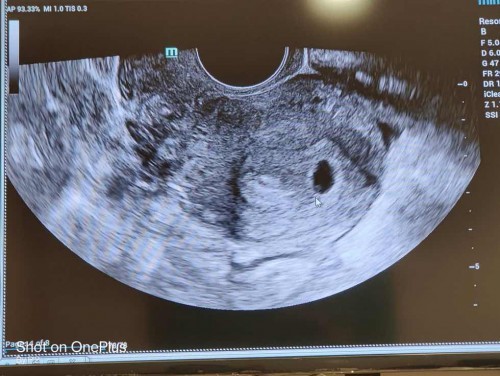

ขอดูใบซาวของแม่ๆอายุครรภ์4-5สัปดาห์หน่อยค่ะเป็นแบบไหน ของเค้ายังไม่เห็นน้องเลยค้า เห็นแต่จุดๆเล็กๆ แม่ลุ้นหนักมากขอให้แม่สมหวังด้วยนะ

เห็นถุงตอน6วีค ตอนนี้13วีคแล้ว ขอให้สมหวังนะค่ะ🥰